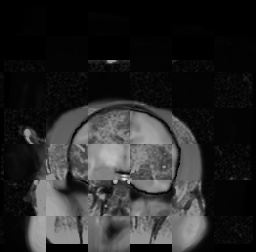

For each of the 10 subjects, we show checkerboard slices in each direction (1) before registration, first row; (2) after rigid->scaleversor->affine registration, second row; and (3) after BSpline registration, third row.

Calvin